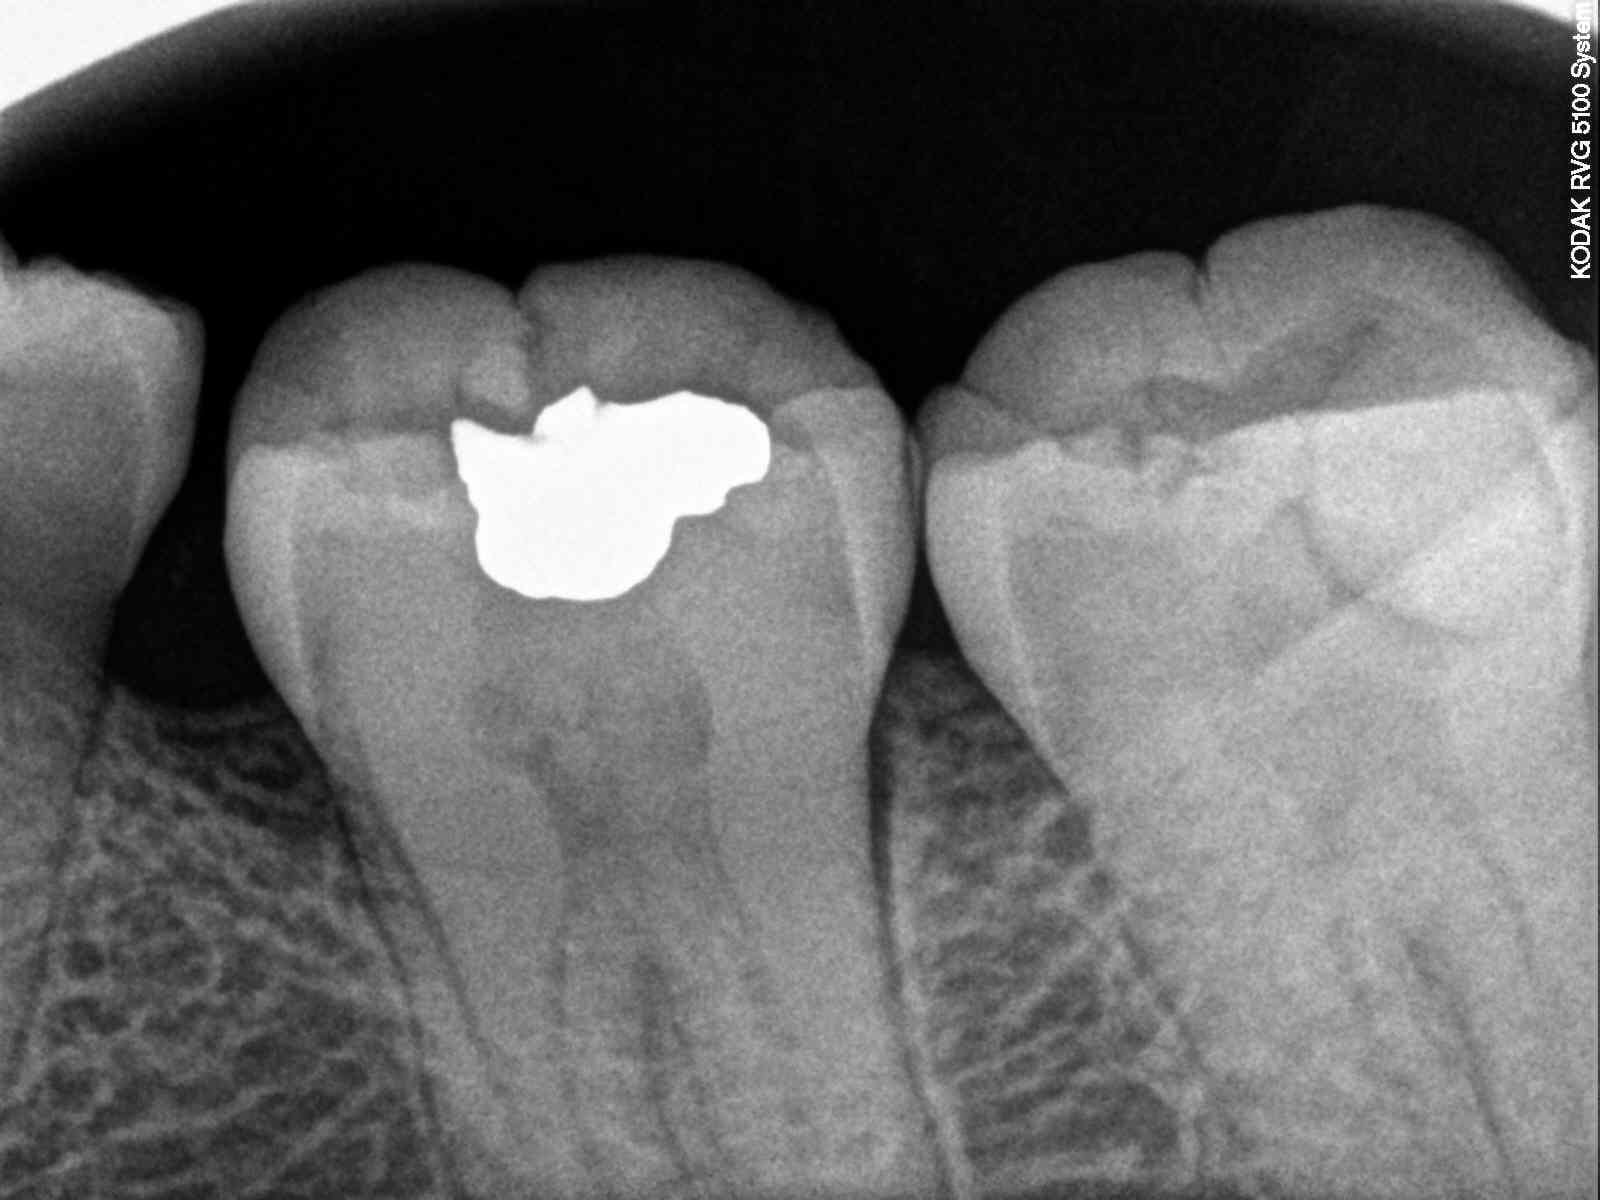

Patiente qui consulte pour douleurs à la mastication sur la 38 qui présente une grosse reconstitution juxtapulpaire.

Globalement la patiente à gagnée 3 ans dans l'affaire qui auraient pu être utilisés à se faire un peut d’épargne pour payer la couronne.

Après le soucis, c'est que la prat qui à fait le précédent soin est absent pour gérer le bébé. Et que le seul acte potentiellement codable pour la sécu est l'extraction de la dent.

Ps, c'etait une nécrose et pas une pulpite encore simple à traiter en urgence.